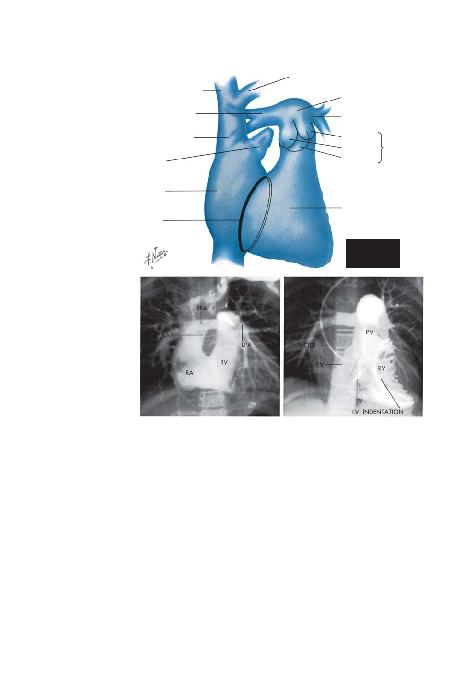

Lateral Projeksiyon (Sayfa 25). Bu görüntü primer ola-

rak sa¤ ventrikülde, sol atriyumda ve kombine sol atriyum

ve sol ventrikülde olan büyümelerin tespitinde kullan>l>r. Ay-

r>ca tomografilerde ve düz filmlerde aort ve mitral kapakta-

ki kalsifikasyonlar> birbirinden ay>rt etmede kullan>labilecek

en görüntüdür. Bu projeksiyonda çekilen selektif bir sa¤

ventriküler angiyokardiyogram>, sa¤ ventrikülün ve pulmo-

ner kapa¤>n d>fla ak>m k>sm>n>n en iyi görüntüsünü verir.

Kalp, sternumun ve omurgan>n kar>fl>kl>k yaratan gölge-

leri olmaks>z>n görüntülenir. Kardiyak silüetin anterior k>sm>

apeks ve sa¤ ventrikülün d>fl ak>m yola¤> taraf>ndan oluflturu-

lur. Normalde, bu yap> anterior gö¤üs duvar>n>n alt dörtte

veya üçte birlik k>sm>na yaslanmaktad>r. Anterior kardiyak

konturun üst üçte ikilik k>sm> yukar> ve posteriora do¤ru

uzanan iki konveks kemer taraf>ndan oluflturulmufltur. Alt

kemer -iki kemerden daha oblik olan>- sa¤ ventirikülün d>fla

ak>m k>sm>nca, üstteki kemer ise asendan aorta taraf>ndan

yap>land>r>lm>flt>r. Bu iki yap> ve sternum aras>nda radyolü-

sen olan akci¤er girmifltir. Sa¤ ventrikül büyü¤ünde ileri

do¤ru genifller ve retrosternal bofllu¤un gittikçe artan bir k>s-

m>n> t>kamaya bafllar. Benzer olarak asendan aortadaki bir di-

latasyon, k>vr>lma veya anevrizma üst retrosternal bofllu¤a

do¤ru büyüyecektir. Büyük damarlar>n orijinin distalinde

olan aort kemerinin üst s>n>r> genelde bu görüntüde tespit

edilebilmektedir.

Kalbin posterior s>n>r> büyük oranda sol atriyumun pos-

terior duvar> taraf>ndan oluflturulur. Diyafram>n hemen üze-

rinde sa¤ atriyumun ve inferior vena kavan>n küçük k>s>mla-

r> görüntüye girer. Ama sol ventrikül geniflledi¤inde posteri-

or olarak sa¤ atriyumdan daha öteye uzanabilir ve böylece

posterior kalp s>n>r>n>n alt k>s>mlar>n> da oluflturabilir. Kalbin

bu konturu en iyi flekilde, ösefagus baryumla dolu iken ince-

lenebilir. Ösefagus sol atriyum ve sol ventrikülün hemen ar-

kas>ndad>r ve bu boflluklardaki genifllemeler ösefagusun an-

terior duvar>nda çentiklenmeye yol açarak, bu organ>n pos-

teriora do¤ru kaymas>na neden olur. E¤er sadece sol atriyum

genifllemiflse ösefagustaki çentiklenme lokalizedir ve kardi-

yak silüetin üst yar>s>nda görülür, ösefagusun alt k>sm> nor-

mal pozisyonundad>r. Sol ventrikülün de büyüdü¤ü durum-

larda ise ösefagus ayn>